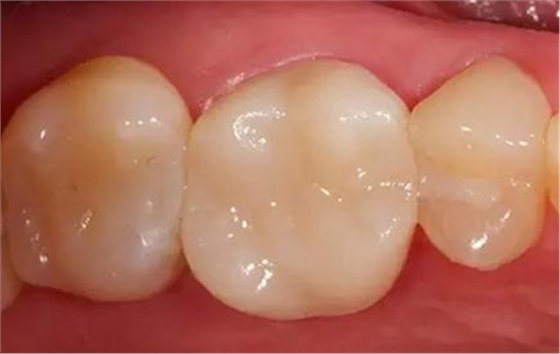

步驟12

最終修復(fù)冠

拋光后的修復(fù)冠。由VITA SUPRINITY材料制作, 選擇1M2-HT。